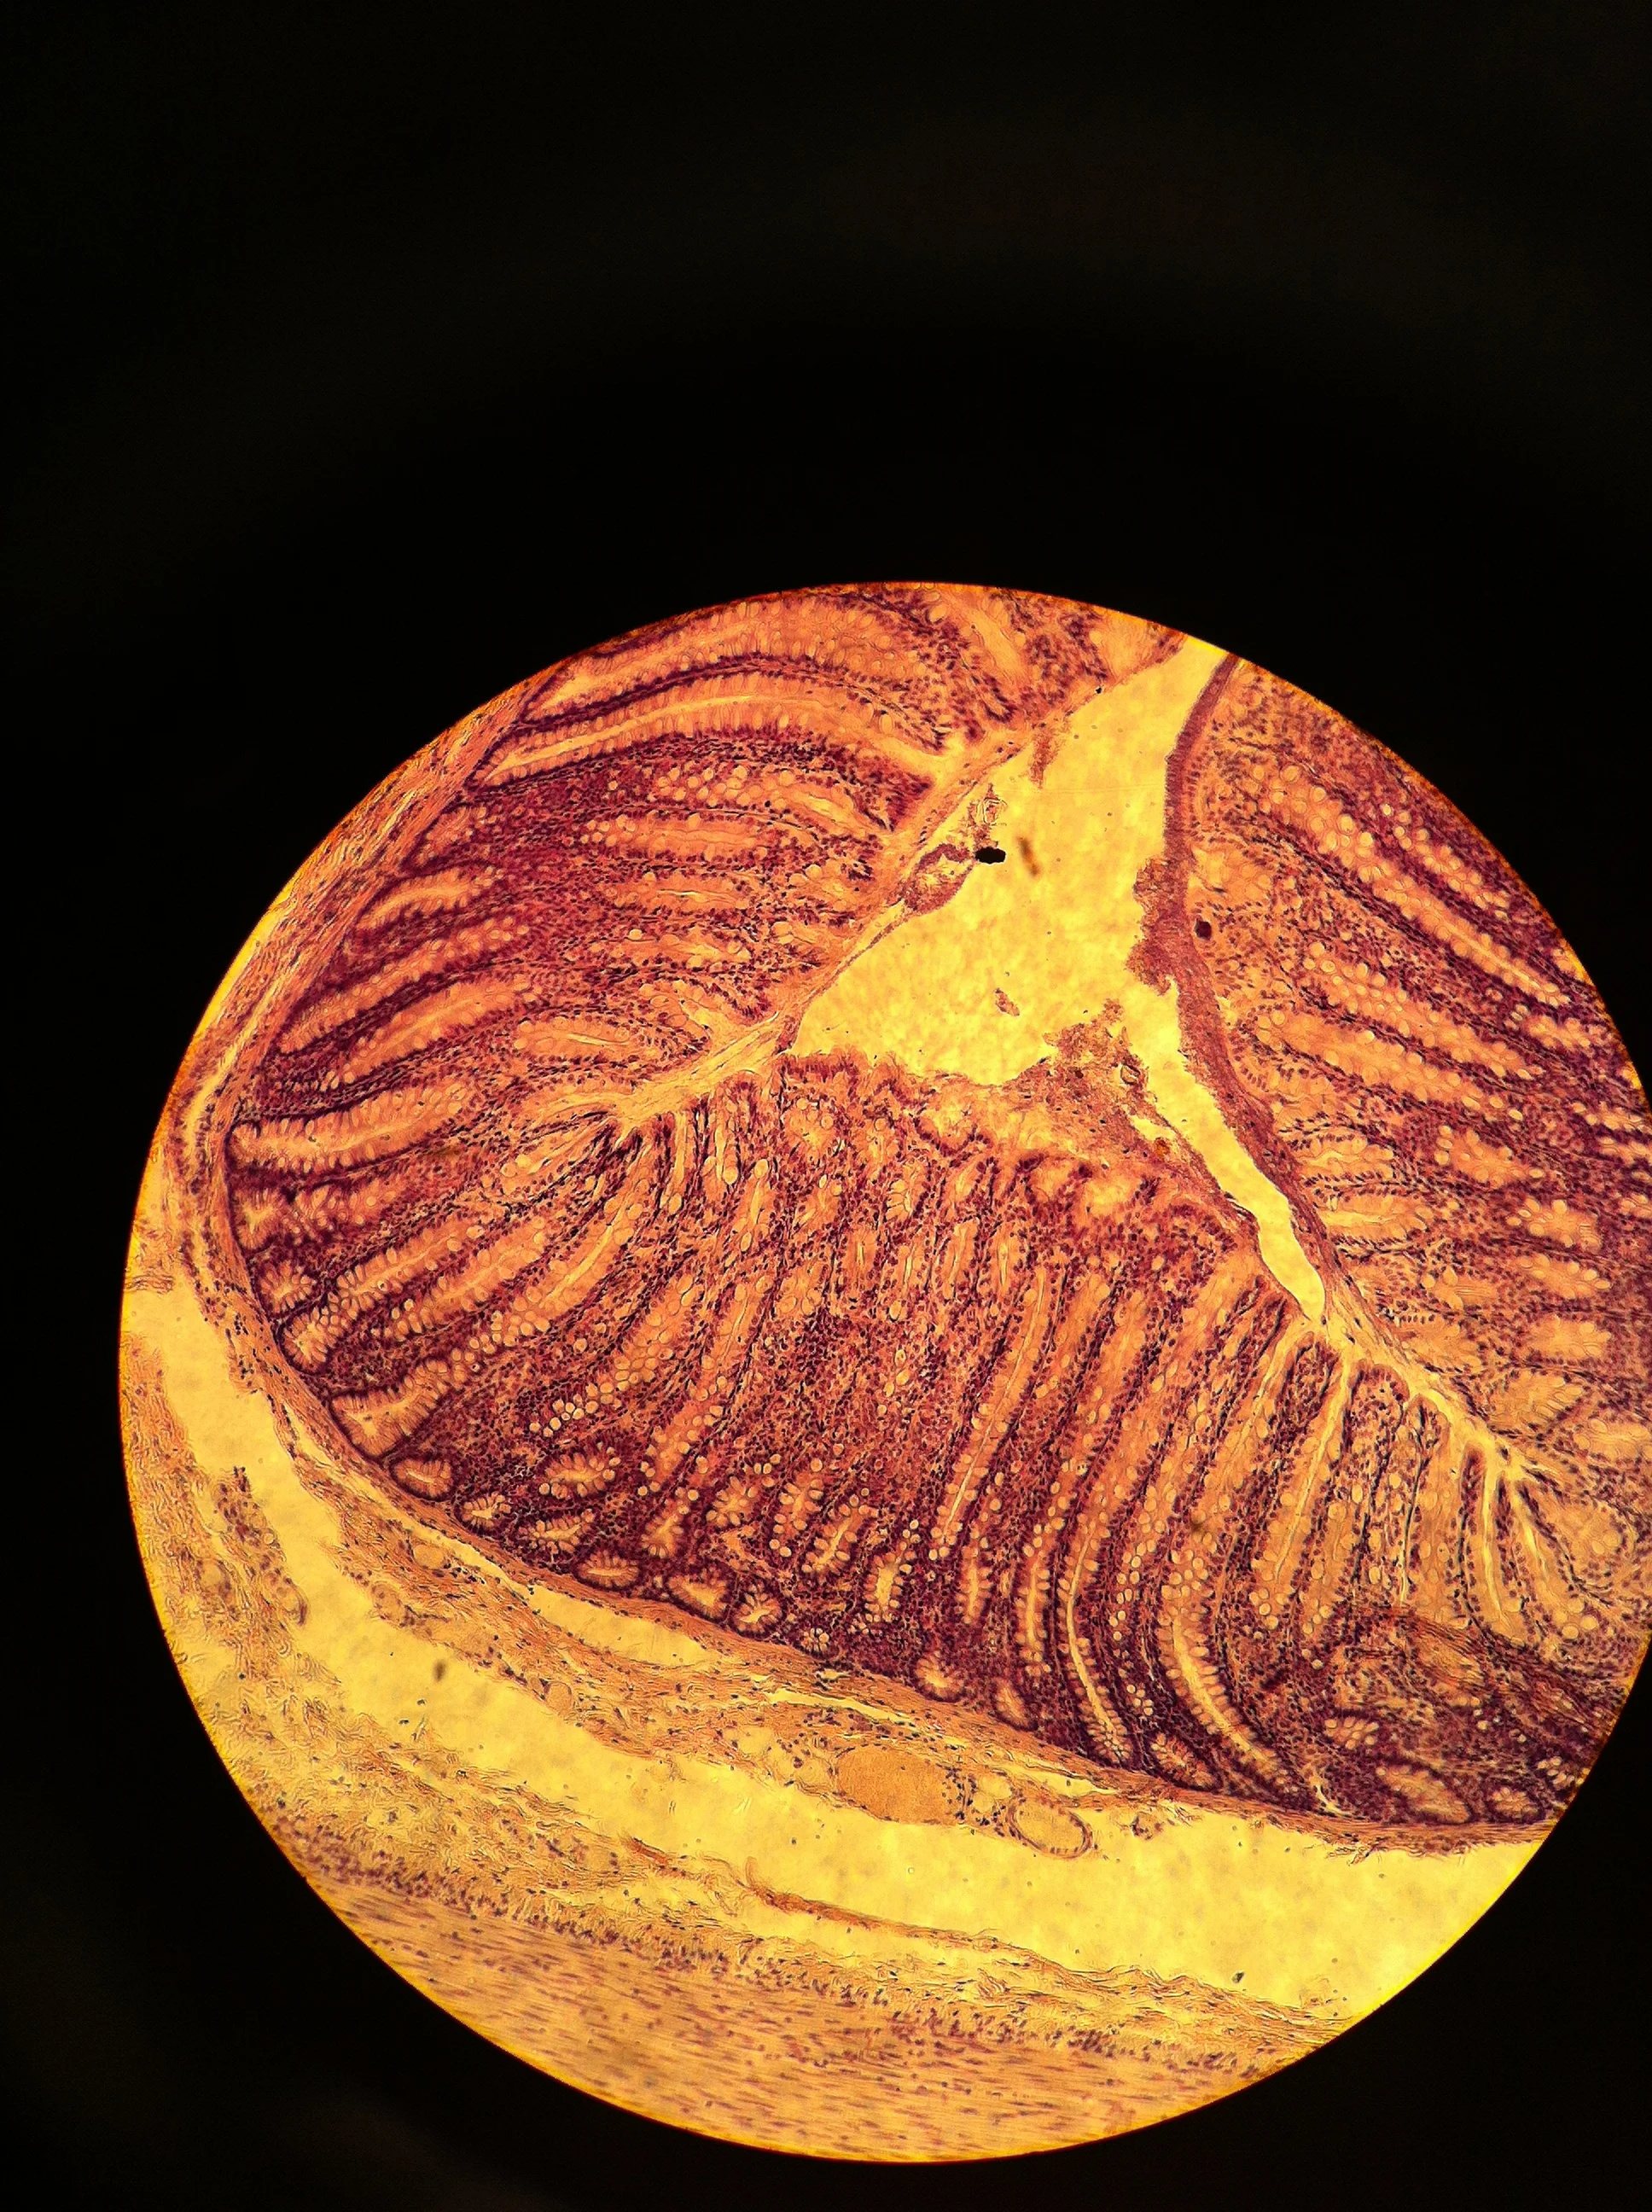

Duodenum 40X